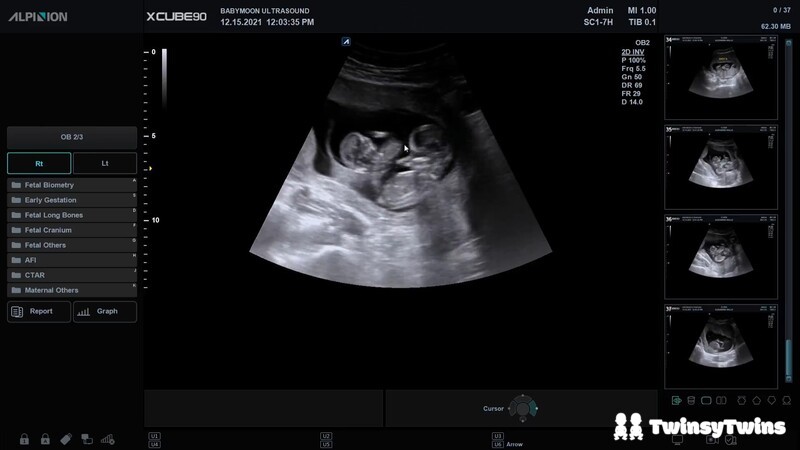

Four years ago, in mid-December, we went in for a fun ultrasound at just shy of 13 weeks' along to take a peek at our baby because I didn't want to wait for our anatomy scan at 20 weeks to see them for the very first time.

Thank goodness we didn't wait. The instant the technician turned on the ultrasound machine and brought the sonogram into focus, she instantly saw what we never saw coming.

She asked if we saw what she saw.

I, naively, pointed out that I could see our baby curled up on their side.

She paused, and said, "Not that."

And then my husband said what she was waiting for us to figure out.

It was twins.

We found out at just shy of 13 weeks' along that we were having twins, and we were absolutely shocked.